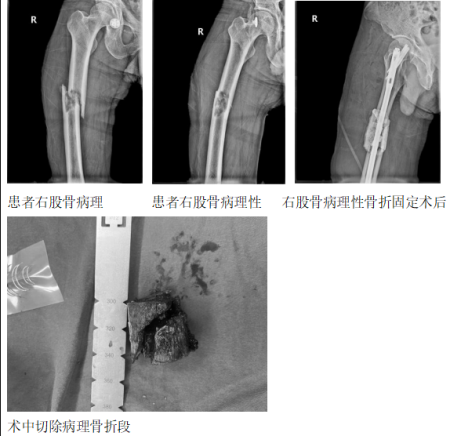

2024年2月6日,这个平凡的日子里,我们收到了一个好消息,家住玉溪市峨山县小街的一位患鼻咽癌2年后发生右侧大腿骨转移病理性骨折的患者,重新站立起来了,这得益于玉溪市人民医院骨外二科团队的专业治疗。

这位患者今年43岁,无意间出现右侧大腿疼痛,休息无好转,之后逐渐加剧直至不能活动,只能躺在床上,后来到玉溪市人民医院就诊,经过相关检查,发现是右侧股骨小转子、脊柱、颅骨多处骨转移。而大腿的疼痛,正是因为鼻咽癌术后骨转移、右侧股骨出现了病理性骨折。听闻结果,患者一度在绝望的边缘徘徊。

2024年2月2日,骨外二科陆景华主任主刀,为患者做了瘤段切除+髓内钉固定+骨水泥充填,术后患者独立辅助行器站立起来,并于年前出院回家。